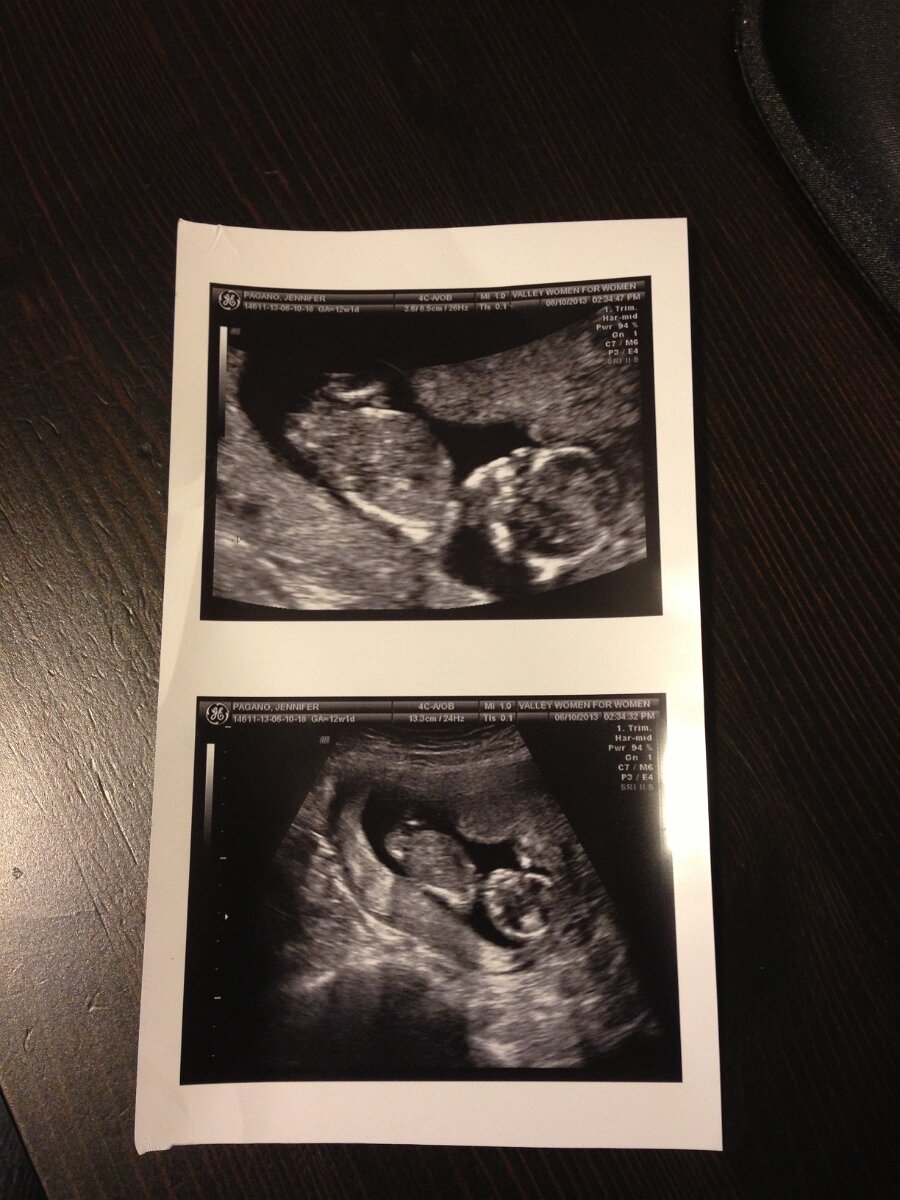

2013-06-10

6/10/13—2/16/19

June 10th

Our Baby